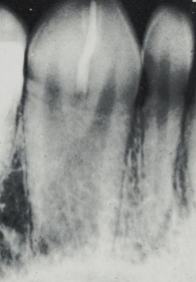

enamel pearl

nodules at furcation of multi-rooted teeth, most common on MAX MOLAR

hypercementosis

a condition characterized by excessive deposition of cementum on root surfaces, associated with GARDNER and PAGET disease